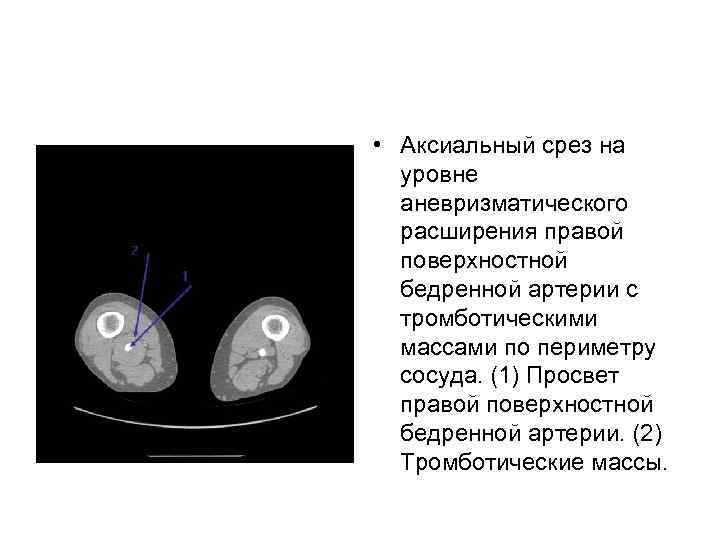

• Аксиальный срез на уровне аневризматического расширения правой поверхностной бедренной артерии с тромботическими массами по периметру сосуда. (1) Просвет правой поверхностной бедренной артерии. (2) Тромботические массы.